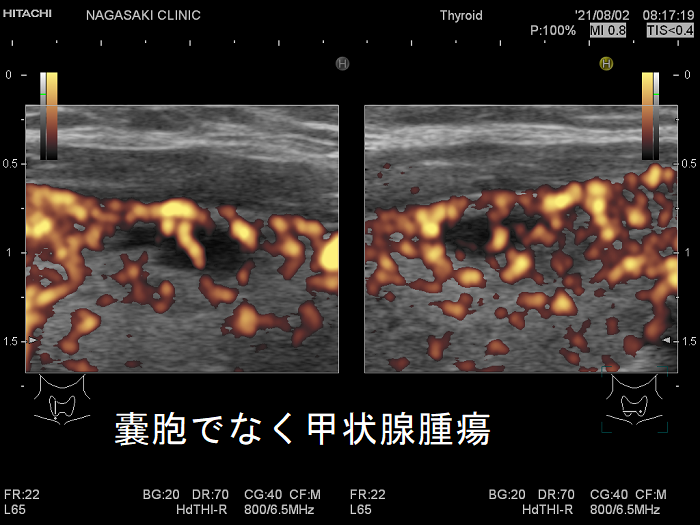

甲状腺のう胞に見えるが実は甲状腺腫瘍

甲状腺のう胞(甲状腺嚢胞)に見えるが甲状腺腫瘍 超音波(エコー)画像;低エコー(真っ黒)で、内部にコロイド様物質があるように見えるため、甲状腺のう胞(甲状腺嚢胞)と間違えます。

甲状腺のう胞に見えるが実は甲状腺腫瘍 eFlow

甲状腺のう胞(甲状腺嚢胞)でなく甲状腺腫瘍  eFlow(イー フロー);内部血流が、はっきり見えて甲状腺腫瘍なのがわかります。

たとえば、通常Bモードでは、

1. のう胞(嚢胞)に見えても、高感度パワードプラーで低流速の細い血管が検出され、実は真っ黒な(極めて低エコーな)甲状腺腫瘍 [甲状腺のう胞(甲状腺嚢胞)に見えるが甲状腺腫瘍]

2. 充実性腫瘍に見えても、高感度パワードプラーで低流速の細い血管が検出されず、実はただの甲状腺のう胞腺腫(甲状腺嚢胞腺腫)(内部の不均質な実質様エコーは粘稠なコロイド物質)

だったなど、臨床診断が覆る場合があります。特に1.の場合は、甲状腺腫瘍甲状腺のう胞(甲状腺嚢胞)と間違えると大変な事になります。極めて低エコーな甲状腺腫瘍は、甲状腺乳頭癌甲状腺濾胞癌甲状腺髄様癌甲状腺悪性リンパ腫の可能性があるからです。